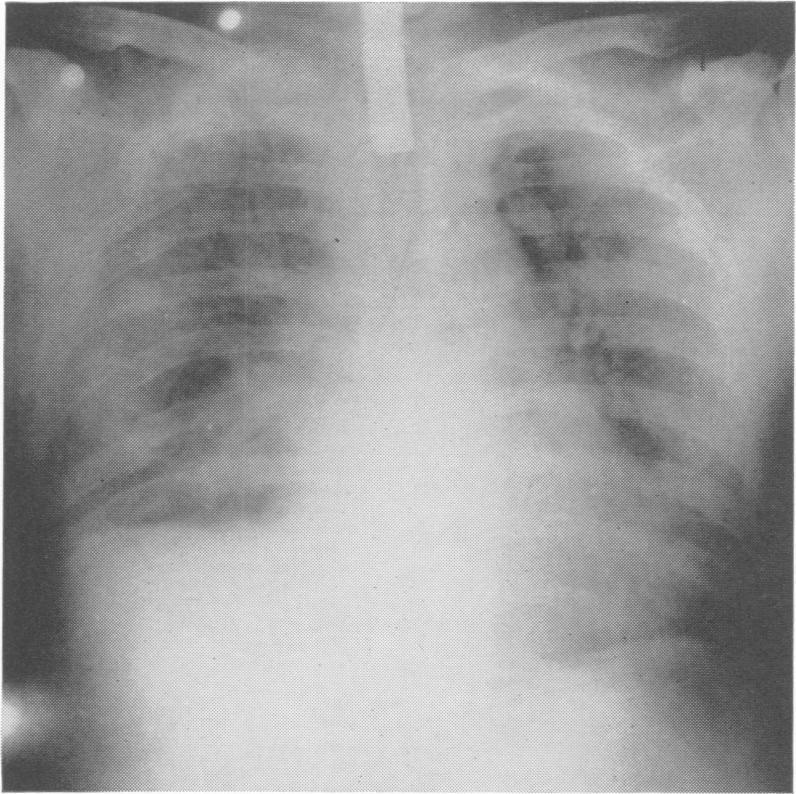

Physiopathology of crushed chest injuries.

Ann Surg. 1968 Jul;168(1):128-36. doi: 10.1097/00000658-196807000-00015.